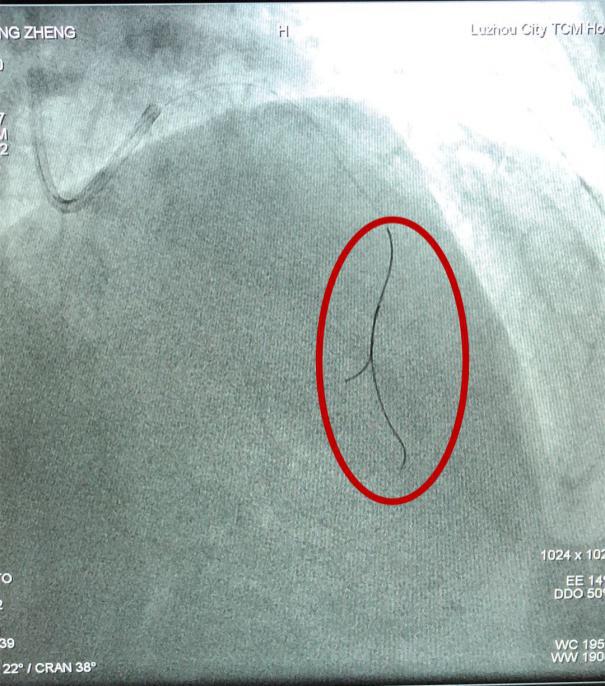

川南首例FFR(冠狀動(dòng)脈內(nèi)壓力導(dǎo)絲直接測量血流儲(chǔ)備分?jǐn)?shù))手術(shù)中

壓力導(dǎo)絲(如圖中紅圈內(nèi)所示)

在冠脈內(nèi)測量FFR(血流儲(chǔ)備分?jǐn)?shù))